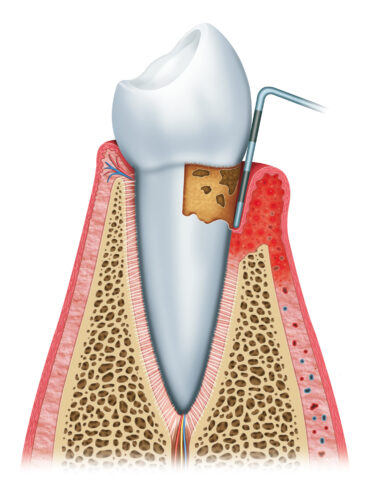

二、輕度牙周炎

此階段細菌已侵入齒槽骨,造成齒槽骨流失,並破壞牙周韌帶,使牙齦與牙齒之間形成一條狹窄的縫隙,稱為牙周囊袋。一旦牙周囊袋產生,牙菌斑就更容易在此堆積,牙刷將很難清潔到此處的死角,牙齦紅腫發炎的情況持續出現,並向更深處的牙周組織蔓延。